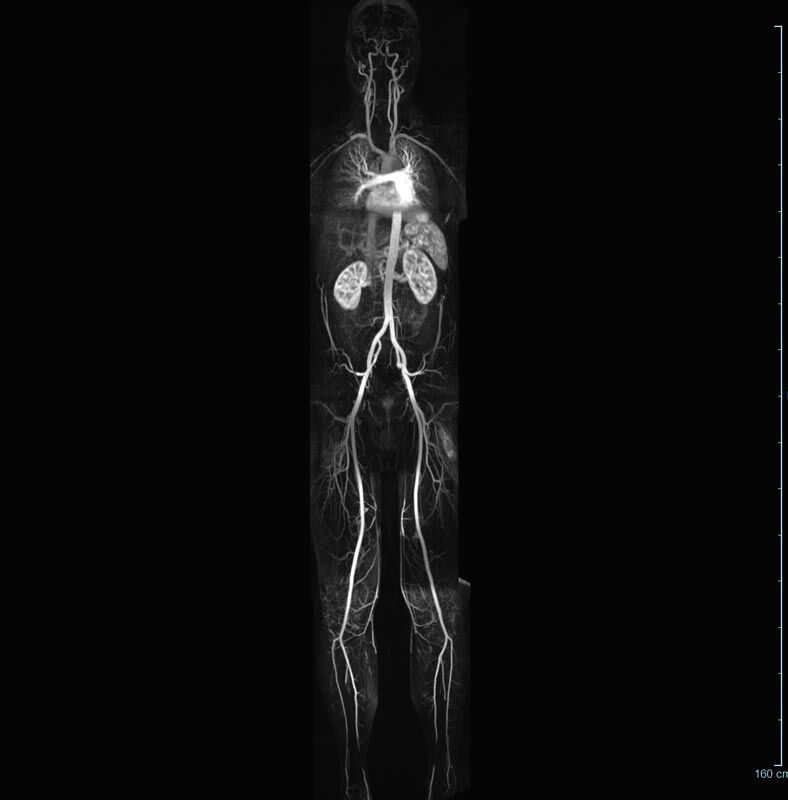

MR-Angiografie (MRA)

• MR-Angiographie mit Kontrastmittel

• Erfassung arterieller und venöser Gefäße/Bypässe aller Körperregionen mit 3D-Rekonstruktion

• Bauchgefäße

• Erfassung und Verlaufskontrolle bei arteriellen Aneurysmen (Aussackungen der Arterien), vor allem der Bauchaorta

• Darstellung von Gefäßengen an Nierenarterien, Baucharterien und Becken-/Beinarterien